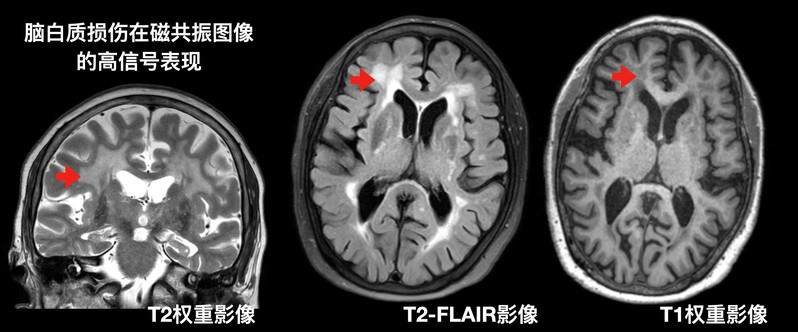

如同脸上的皱纹一样,随着年龄增长,大脑也会发生如灰白质萎缩等老化现象,并可反映在磁共振图像中。其中,大脑白质高信号属于一种磁共振图像中肉眼可见的常见脑白质老化表征。这种特征在磁共振T2权重影像中表现为高信号,临床通常采用水抑制的T2权重扫描序列(T2-FLAIR)突出其对比性以利临床判读(图1)。白质高信号被认为是起源于白质损伤,发生损伤的原因主要为神经血管功能退化包括髓鞘或轴突丢失、组织稀疏、神经胶质增生、短暂脑梗或大脑血流长期低灌注。白质损伤不仅影响灰质间神经纤维的沟通效率,更被证实为认知障碍、抑郁甚至痴呆症的关键风险因子。

图1、脑白质损伤在临床常用的磁共振图像显而易见,如图中红色箭头标示的即为异常大脑白质信号位置。在T2权重序列中呈现高信号,在T1权重影像上呈现异常低信号。